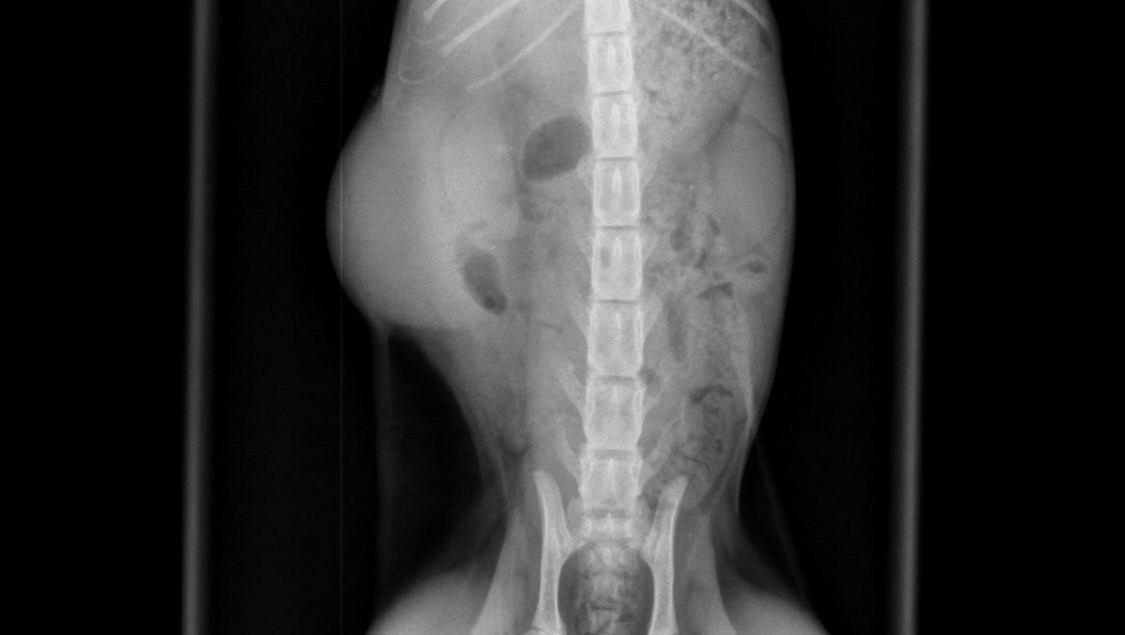

Everything was going well and she was about to be discharged when she crashed and her hematocrit dropped from 30 to 12. She was then in the ICU battling life threatening anemia. Her ultrasound showed abnormal changes in the spleen. After careful discussion the vet said there is a strong possibility of FIP because of all the trauma she had been through and decided to start her on GS 441524 treatment for 84 days. Remi greatly improved on GS injections and the diagnosis of dry FIP was confirmed.

By then Remi’s bill had already reached close to 5500 aed (£1200). Unfortunately after a whole month her abscess got reinfected and had to be drained again. The vet then decided to send her samples for a culture and sensitivity test to idexx, UK and it was shown that she had two different types of bacteria that need another round of a very specific antibiotic- gentamycin